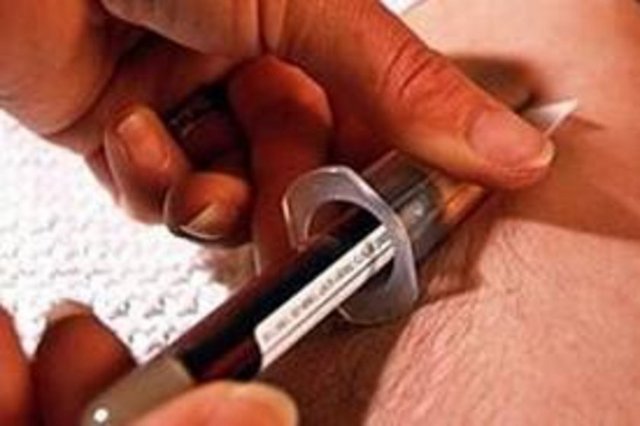

Mutlaka kan sayımınızı yaptırın

Basit bir kan sayımıyla kansızlık teşhis edilebilir. Altta yatan nedeni öğrenmek için kan testleri yapılması gerekir. Kronik kansızlığın tedavisinde, kansızlığa yol açan rahatsızlığın düzeltilmesi gerekir.